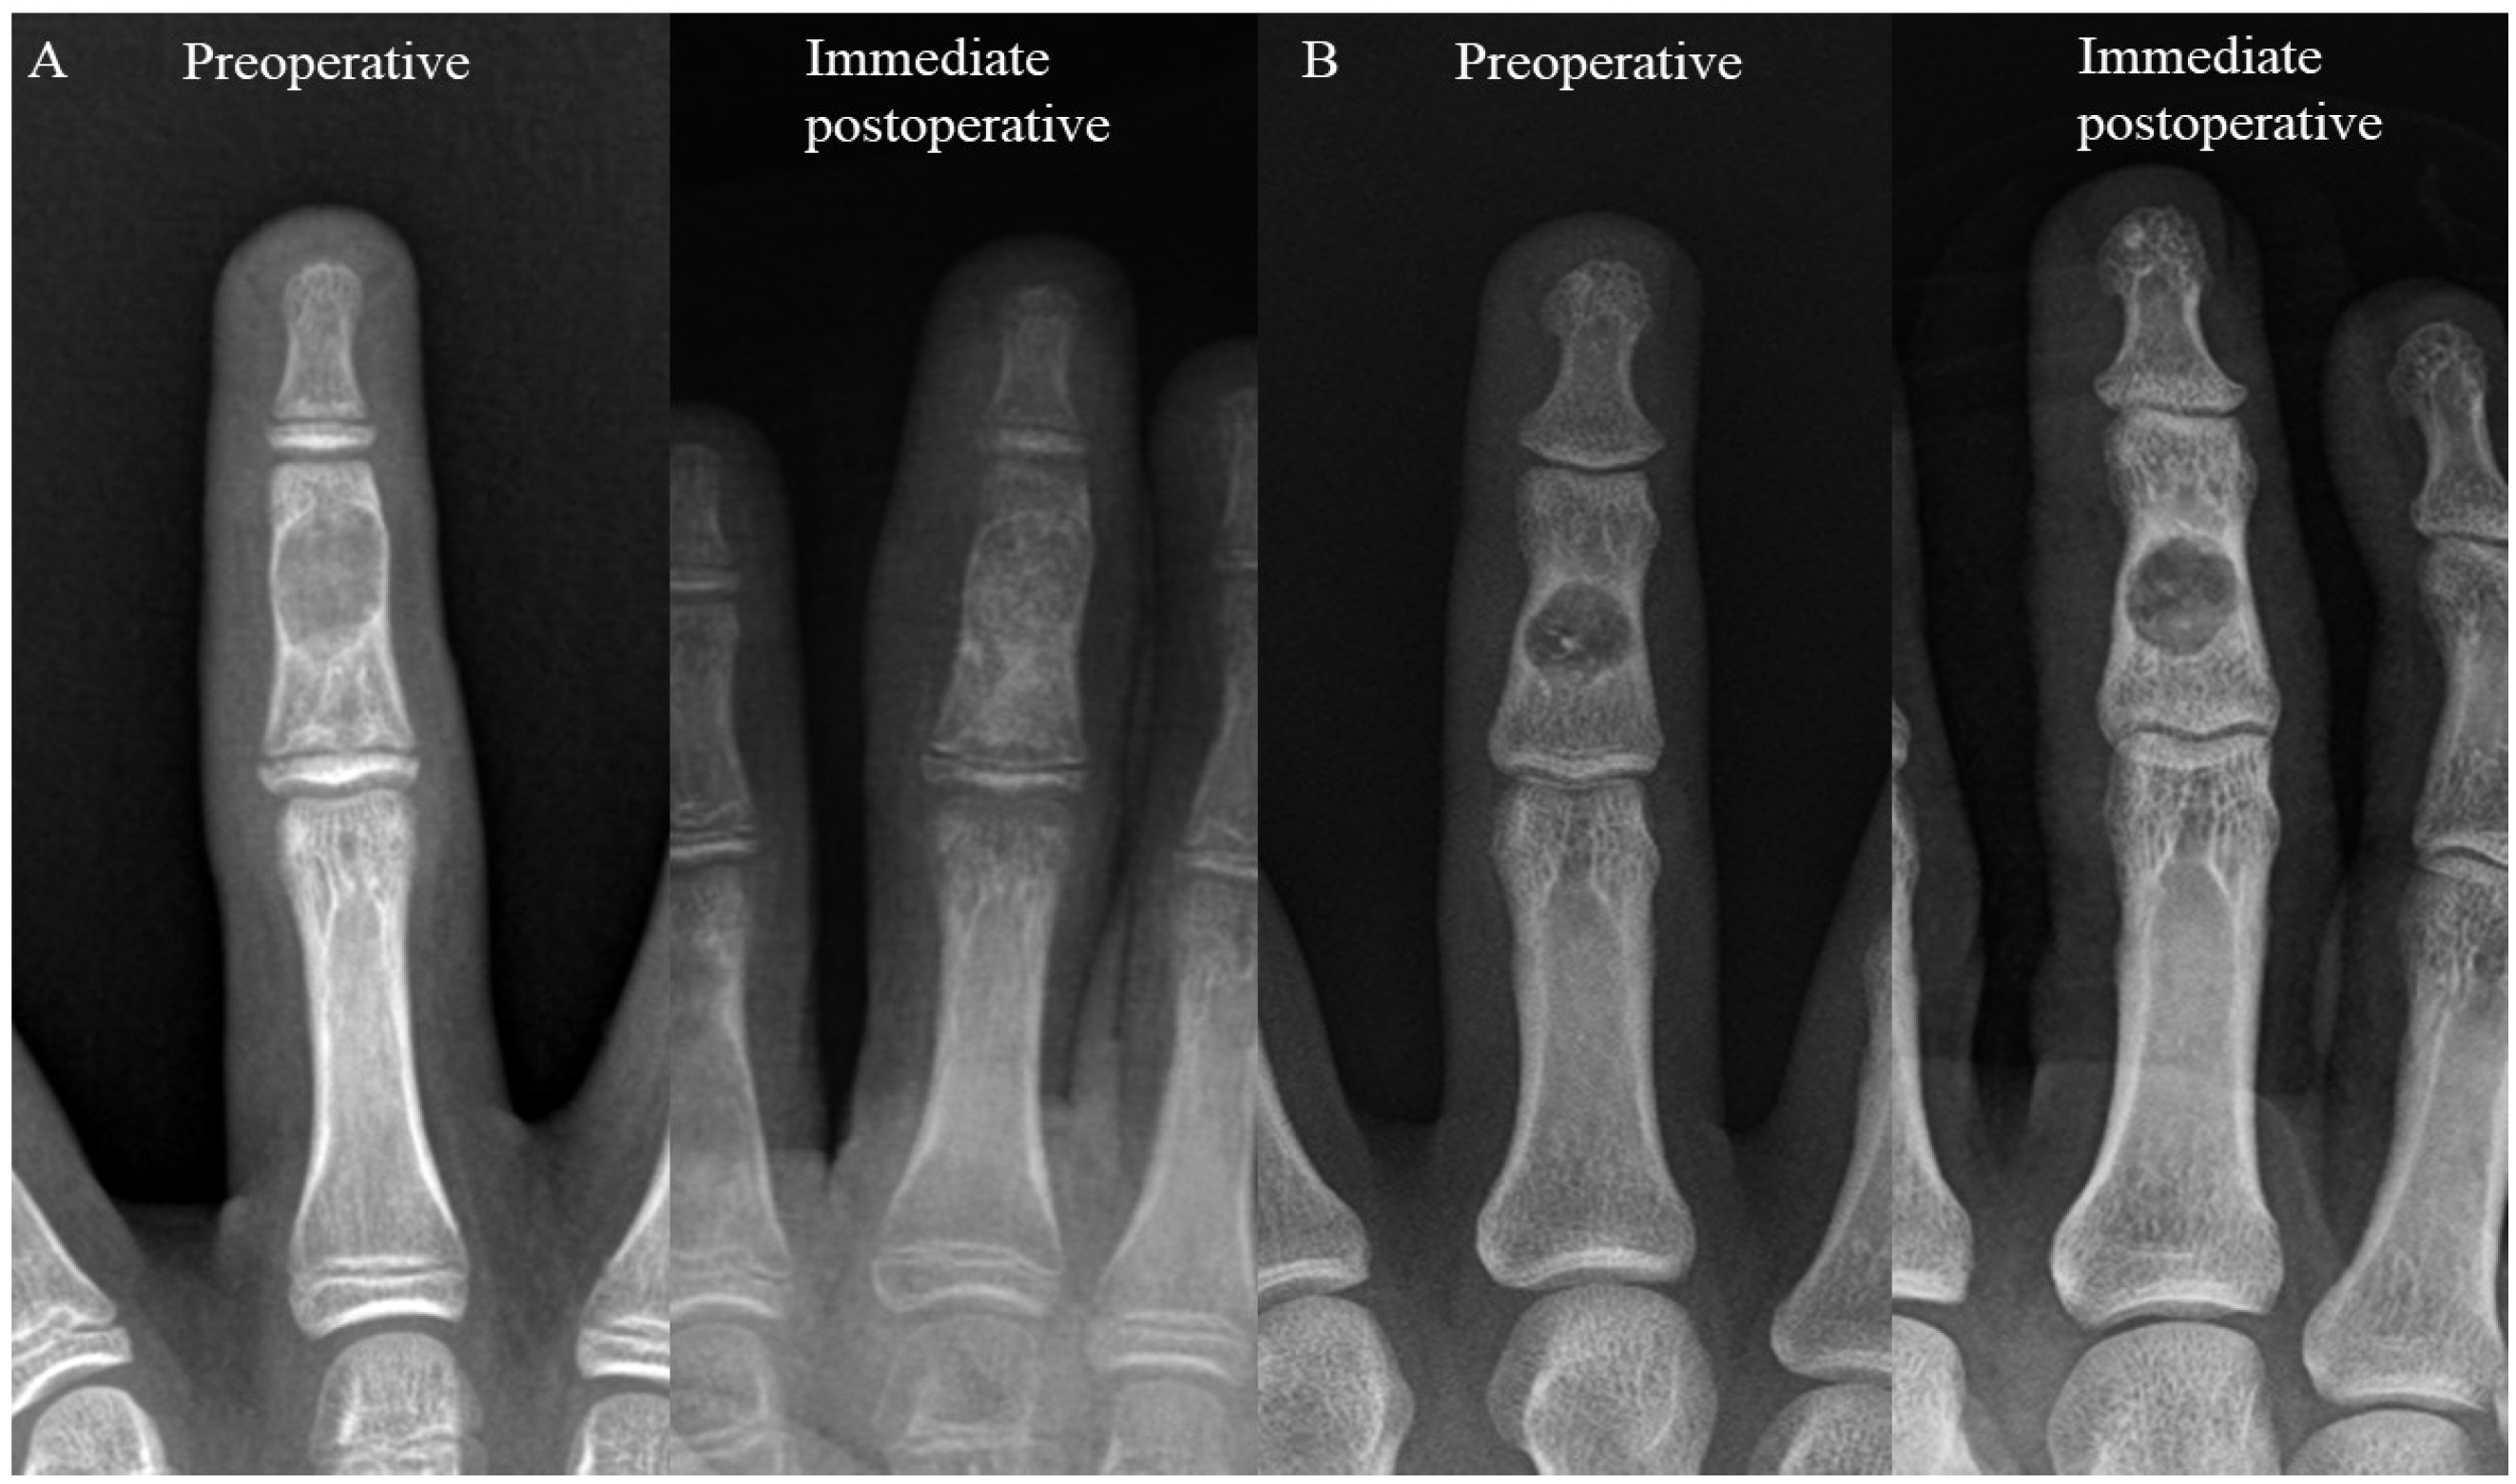

2.1. Surgical Procedure and Rehabilitation

2.2. Radiographic Evaluation